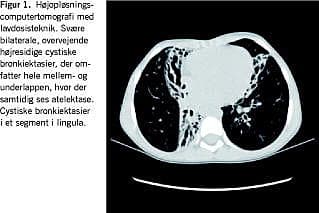

Røntgen af thorax viste bilaterale infiltrater og en højresidig mellem- og underlapsatelektase. Efterfølgende højopløsnings-computertomografi af thorax med stråleskånsom lavdosisteknik viste bilaterale omfattende cystiske bronkiektasier med kollaps af tilhørende lungeparenkym (Figur 1). Lungestetoskopien var med bilateral, spredt krepitation.

Tuberkulose, immundefekt og cystisk fibrose (CF) blev udelukket. Pigen blev derefter henvist til Dansk Børnelungecenter, Rigshospitalet (DBLC) til videre udredning og diagnosticeret med primær ciliedyskinesi (PCD).